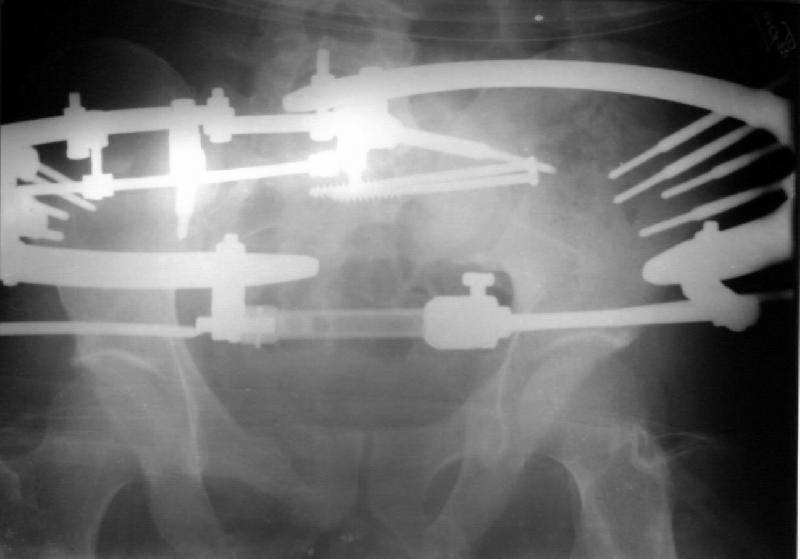

An example of our current approach to similar injuries - A 26 y.o. male admitted to us Aug 23, 2001 6 weeks after injury (compression by a wheel of a truck).

An external fixator was applied and gradual reduction was started - lateral traction to mobilize sacral fracture and then the hemipelvis was moved downward. Then lateral compression was performed. Yesterday iliosacral screws was inserted.

The last couple of images are skewed, they were made in OR and patient was not properly positioned.